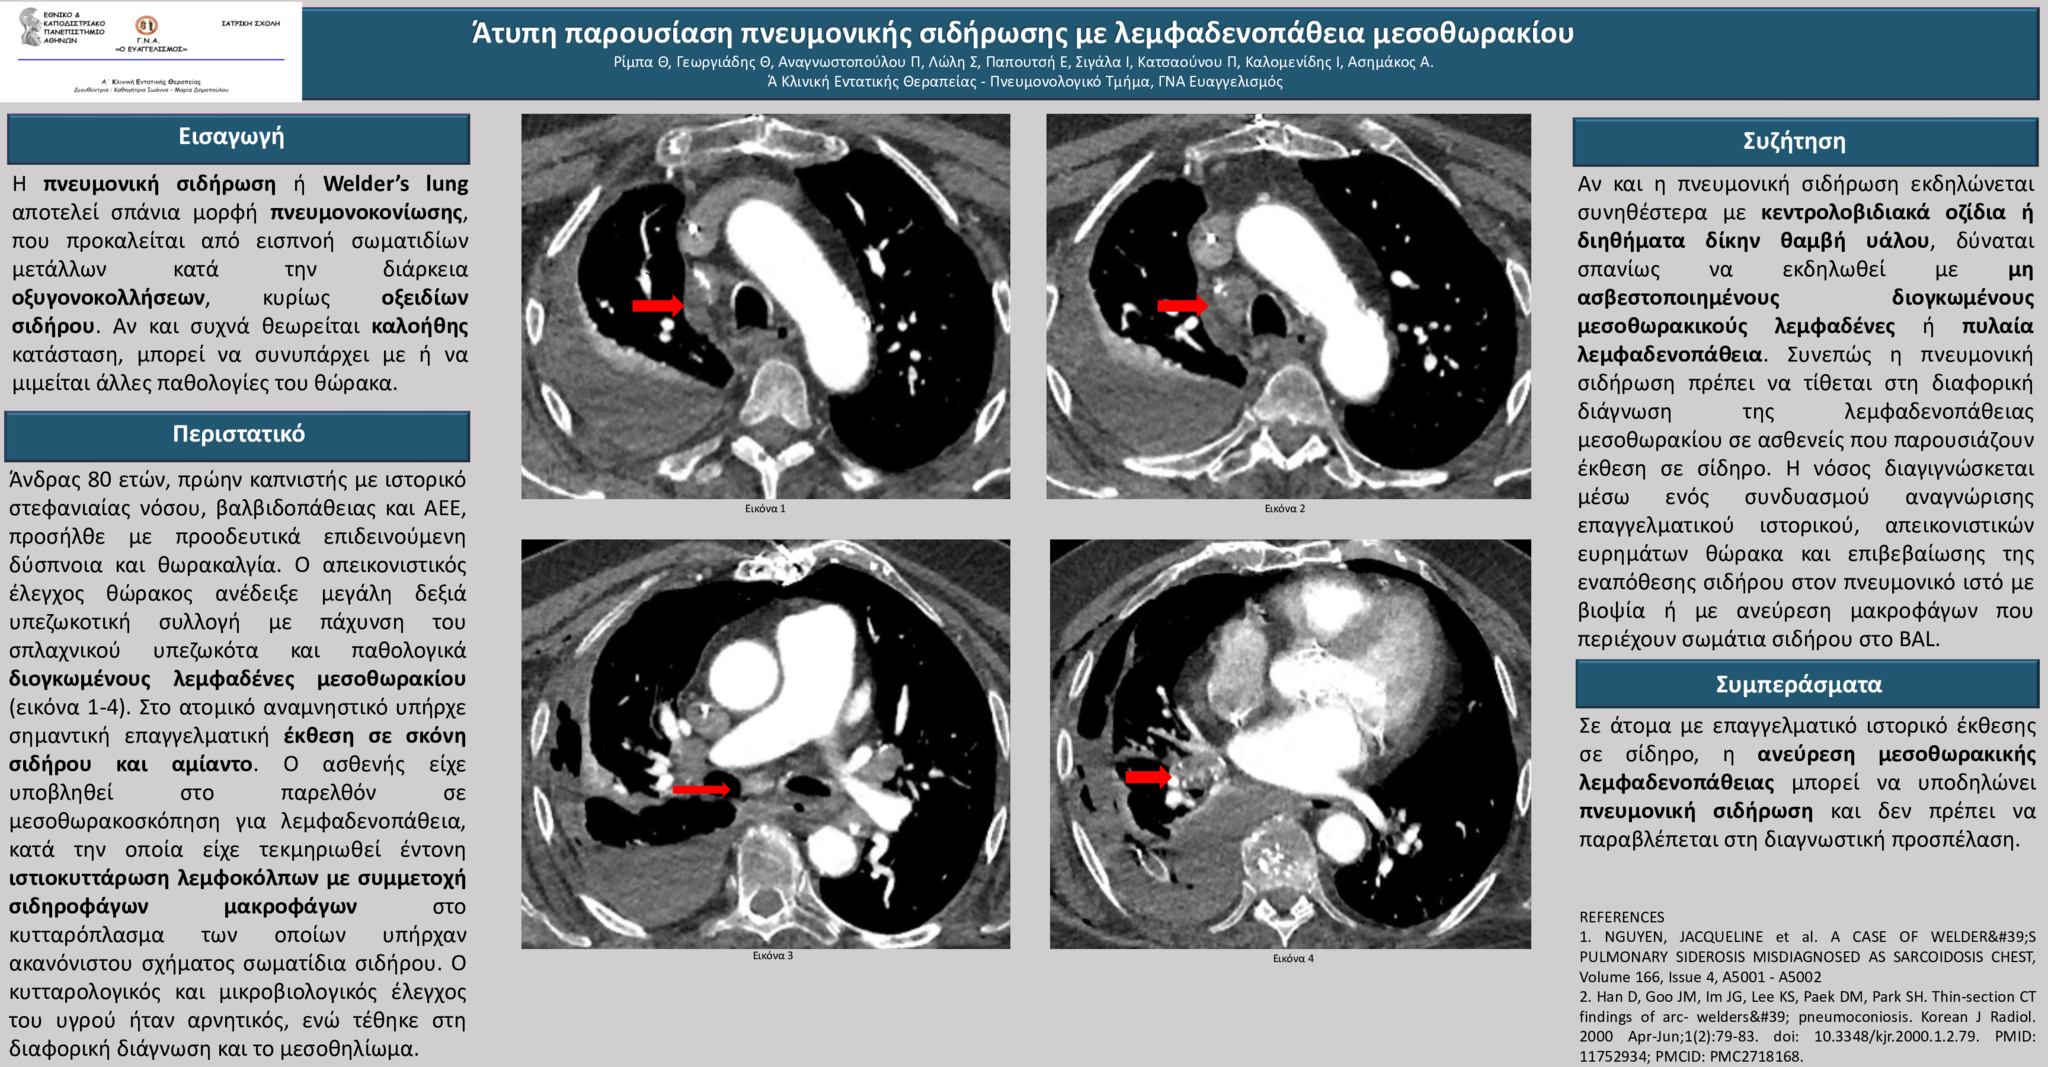

Περίπτωση: Άνδρας 80 ετών, πρώην καπνιστής με ιστορικό στεφανιαίας νόσου, βαλβιδοπάθειας και αγγειακού εγκεφαλικού επεισοδίου, προσήλθε με προοδευτικά επιδεινούμενη δύσπνοια και θωρακαλγία. O απεικονιστικός έλεγχος θώρακος ανέδειξε μεγάλη δεξιά υπεζωκοτική συλλογή με πάχυνση του σπλαχνικού υπεζωκότα και παθολογικά διογκωμένους μεσοθωρακικούς λεμφαδένες. Στο ατομικό ιστορικό υπήρχε σημαντική επαγγελματική έκθεση σε σκόνη σιδήρου και αμίαντο. Ο ασθενής είχε υποβληθεί στο παρελθόν σε μεσοθωρακοσκόπηση για λεμφαδενοπάθεια, κατά την οποία είχε τεκμηριωθεί έντονη ιστιοκυττάρωση λεμφοκόλπων με συμμετοχή σιδηροφάγων μακροφάγων στο κυτταρόπλασμα των οποίων υπήρχαν ακανόνιστου σχήματος σωματίδια σιδήρου. Ο κυτταρολογικός και μικροβιολογικός έλεγχος της συλλογής ήταν αρνητικός, ενώ τέθηκε στη διαφορική διάγνωση και το μεσοθηλίωμα Συζήτηση: Αν και η πνευμονική σιδήρωση εκδηλώνεται συνηθέστερα με κεντρολοβιδιακά οζίδια ή διηθήματα δίκην θαμβή υάλου, δύναται σπανίως να εκδηλωθεί με μη ασβεστοποιημένους διογκωμένους μεσοθωρακικούς λεμφαδένες ή πυλαία λεμφαδενοπάθεια. Συνεπώς η πνευμονική σιδήρωση πρέπει να τίθεται στη διαφορική διάγνωση της λεμφαδενοπάθειας μεσοθωρακίου σε ασθενείς που παρουσιάζουν έκθεση σε σίδηρο. Η νόσος διαγιγνώσκεται μέσω ενός συνδυασμού αναγνώρισης επαγγελματικού ιστορικού, απεικονιστικών ευρημάτων θώρακα και επιβεβαίωσης της εναπόθεσης σιδήρου στον πνευμονικό ιστό με βιοψία ή με ανεύρεση μακροφάγων που περιέχουν σωμάτια σιδήρου στο BAL.

Συμπεράσματα: Σε άτομα με επαγγελματικό ιστορικό έκθεσης σε σίδηρο, η ανεύρεση μεσοθωρακικής λεμφαδενοπάθειας μπορεί να υποδηλώνει πνευμονική σιδήρωση και δεν πρέπει να παραβλέπεται στη διαγνωστική προσπέλαση.